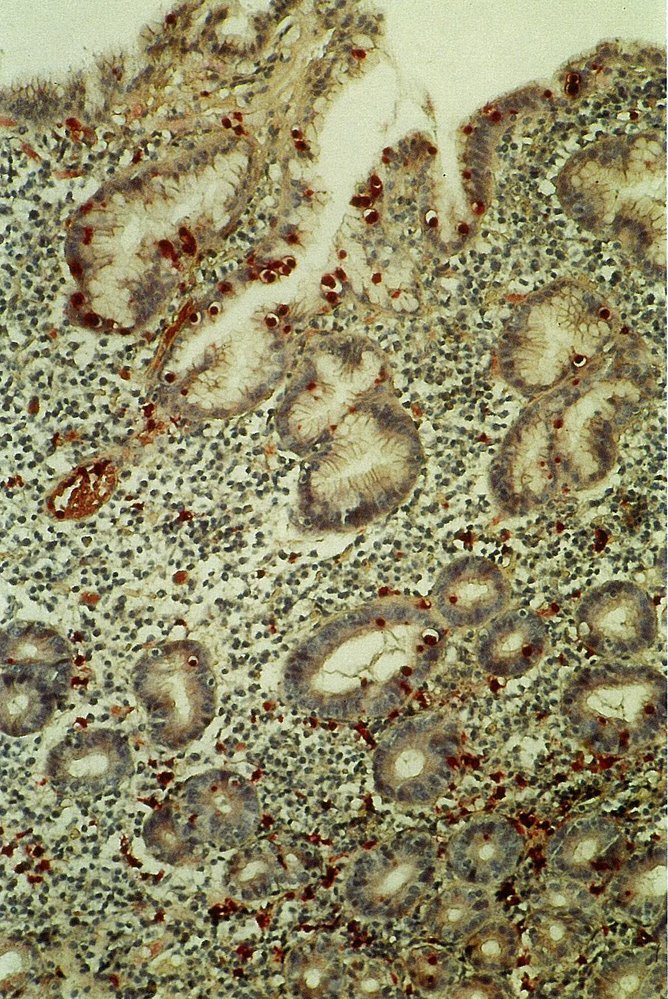

Microscopy findings

The following microscopic findings may be seen in both types of atrophic gastritis.

• Chronic inflammation → granulocytic infiltrations in the mucosa, lymphocytic infiltrations in the submucosa

• Mucosal thinning

• Loss of glands

• Epithelial metaplasia

• (Pseudo)pyloric: replacement of parietal and chief cells in oxyntic glands by mucus-secreting cells, which are usually present in the pyloric region

• Intestinal: replacement of epithelial cells in the oxyntic or antral mucosa by intestinal epithelium cells (e.g., goblet cells)

• Possible detection of H. pylori (gram-negative, rod-shaped bacteria)

• G-cell hyperplasia (common in AIG)